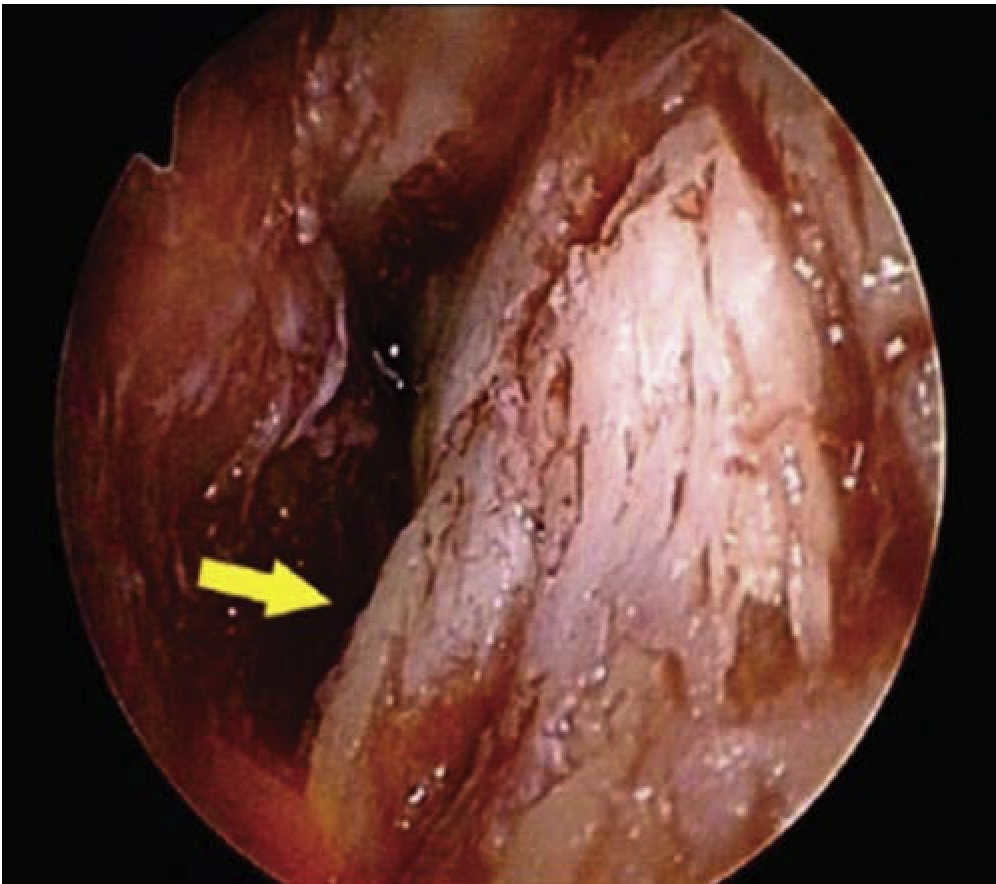

Minimally invasive procedure conducted with endoscopy-assisted tunnel6 (2012)

This technique was published in 2012. It can be considered the most conservative technique when compared with others; it decreases trauma to periodontal tissues during trans-surgical periods and post-operative discomfort, as well as surgical time since it can be accomplished in about 26 minutes.

This technique was first described in 2010. Computed tomography (Cone-Beam) will be needed in order to consider a patient as a possible candidate. Criteria to take into account are the following: Teeth to be moved and anchorage teeth, periodontal circumstances, root position and morphology as well as width of cortical bone.

Advantages of this technique are: decrease of surgical time, periodontium preservation, since it is not required to raise a muco-periosteal flap, patient's easy acceptance of the technique, maximum decrease of post-surgery inflammation since the technique is performed only in the upper or lower anterior section.6

In order to execute this technique, a 5-10 mm full-thickness vertical incision is performed from a vestibular approach at the upper midline to treat the anterior segment, or behind the upper canine in cases when the posterior segment is to be treated. A sub- periosteal dissection is performed on the roots of the teeth with a sharp periosteal elevator (Figure 19A), a full thickness vertical incision is performed from a vestibular approach on the midline (Figure 19B). A «tunnel» sub-periosteal dissection is performed.

After this, an electrical micro-saw is introduced into the created tunnel and vertical corticotomies are executed from a vestibular approach following the length of the root, without touching the alveolar crest (Figures 19C and D).6

With the help of an endoscope through 1.9 mm optic fiber it is possible to control cuts on cortical bone, when the saw reaches cancellous matter, bleeding can be observed by means of the endoscope (Figure 20).6

If resistance is met by the micro-saw, it means that it was placed on root surfaces, therefore, direction of cuts must be changed. Computerized tomography is used to assess corticotomy depth. Lastly, incisions are uninterruptedly sutured with 5-0 polyglactine (Figure 21).6

This technique is presented as the most conservative. Small incisions are performed with the piezoelectrico in the cortical bone. Number of incisions will depend on amount and placement of teeth in the quadrant to be treated. Light afforded by the endoscope and wider image are important advantages as well as achieving better control in root position.